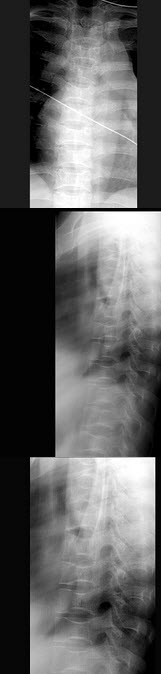

195、单项选择题

婴儿出生后无胎粪,哭闹,腹胀,无肛门。影像检查如图,最可能的诊断为()

A.先天性肛门直肠畸形-高位型

B.先天性肛门直肠畸形-低位型

C.先天性肛门直肠畸形-第5型

D.先天性肛门直肠畸形-第6型

E.先天性肠闭锁